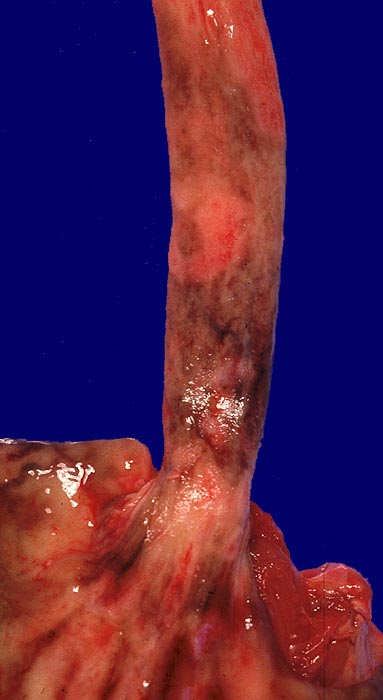

• Teils ulzerierte, teils erodierte Ösophagusmukosa.

Makroskopie